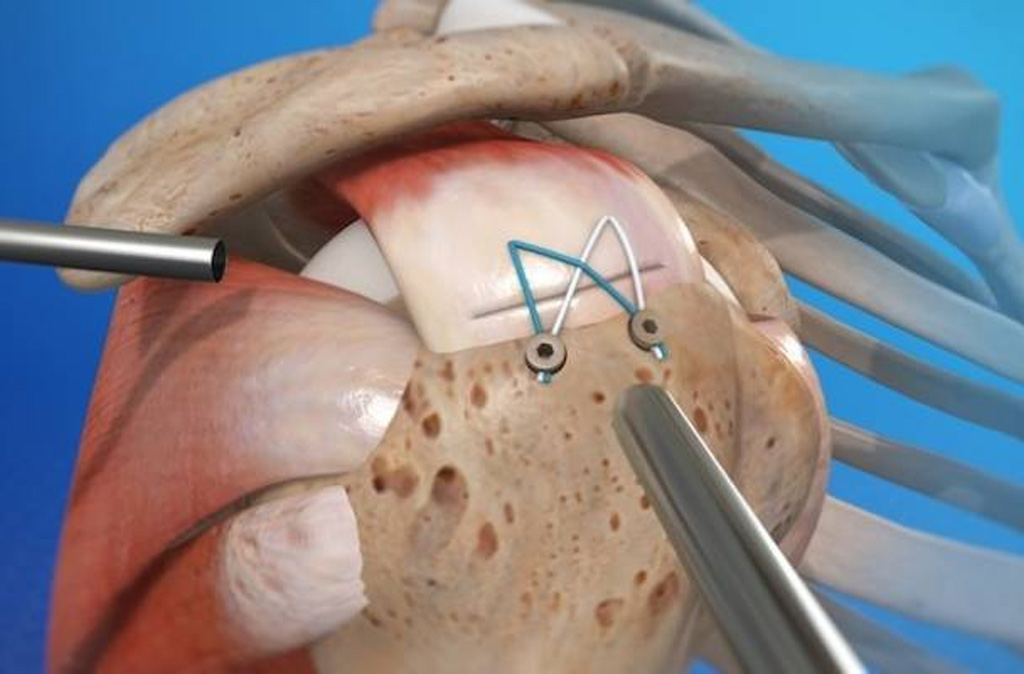

Diz ve omuz artroskopisi

Kapalı cerrahi yöntemlerle menisküs ve bağ yırtıklarının hızlı tedavisi.